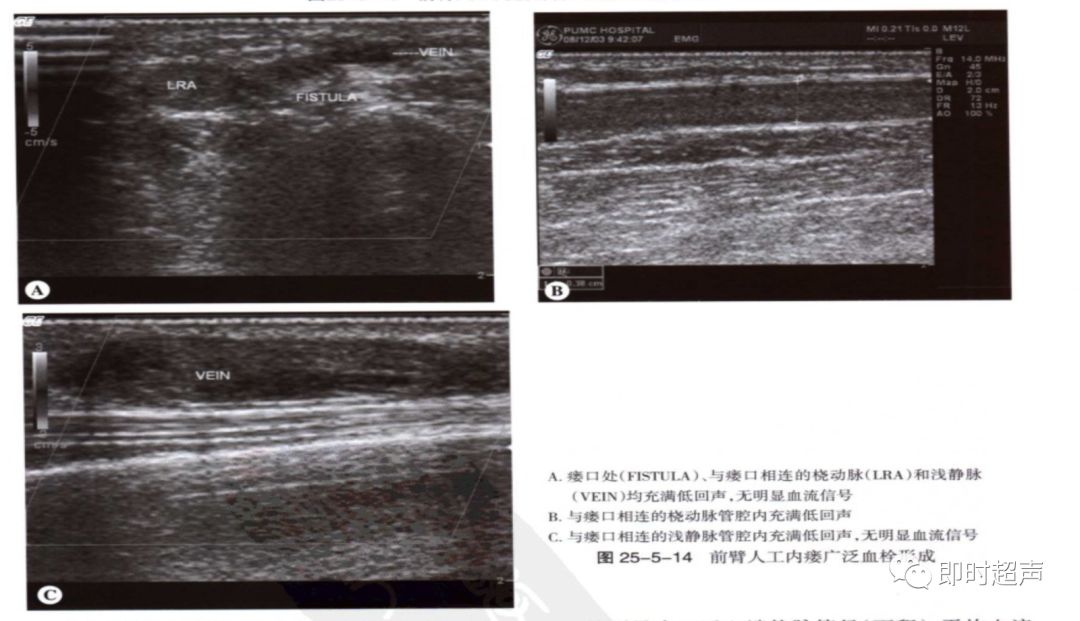

血栓:血栓与狭窄密切相关,常发于静脉侧,静脉管腔压瘪可除外血栓形成。闭塞处可见彩色多普勒血流中断,频谱多普勒信号消失。流入道动脉呈高阻频谱改变。